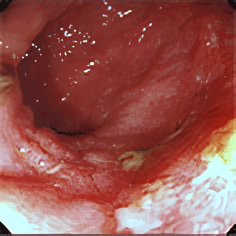

潰瘍性大腸炎

潰瘍性大腸炎の内科的治療と手術のタイミング

潰瘍性大腸炎(Ulcerative Colitis、以下UC)は、厚生労働省により特定疾患と認定されていますが、患者数は年々増加し現在8万人前後と言われています。